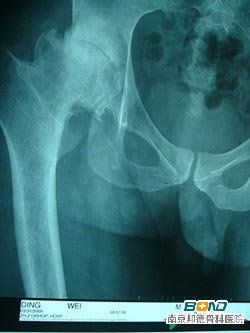

髋关节僵硬常会引起疼痛、跛行、关节功能障碍等,常误诊为坐骨神经痛、腰椎间盘膨(脱)出症、梨状肌综合症等。实际其为股骨头坏死的主要症状之一。

专家指出,由于现代人缺乏运动锻炼及坐姿、走姿等意识,使血液不能正常循环,导致关节和肌肉萎缩,造成髋关节等部位僵硬,从而形成了股骨头坏死。此外,髋关节僵硬的患者可能是由天生畸形导致的,也有一部分是酗酒、使用激素等原因所引发。

目前治疗股骨头坏死的方法有多种,如保守治疗的皮牵引、电刺激、减停激素等;手术治疗的植骨术、截骨术、髋关节形成术等。在治疗期间前后,患者应进行功能锻炼,其目的是防止组织粘连、肌肉萎缩、关节僵硬,改善关节营养供给的功能。